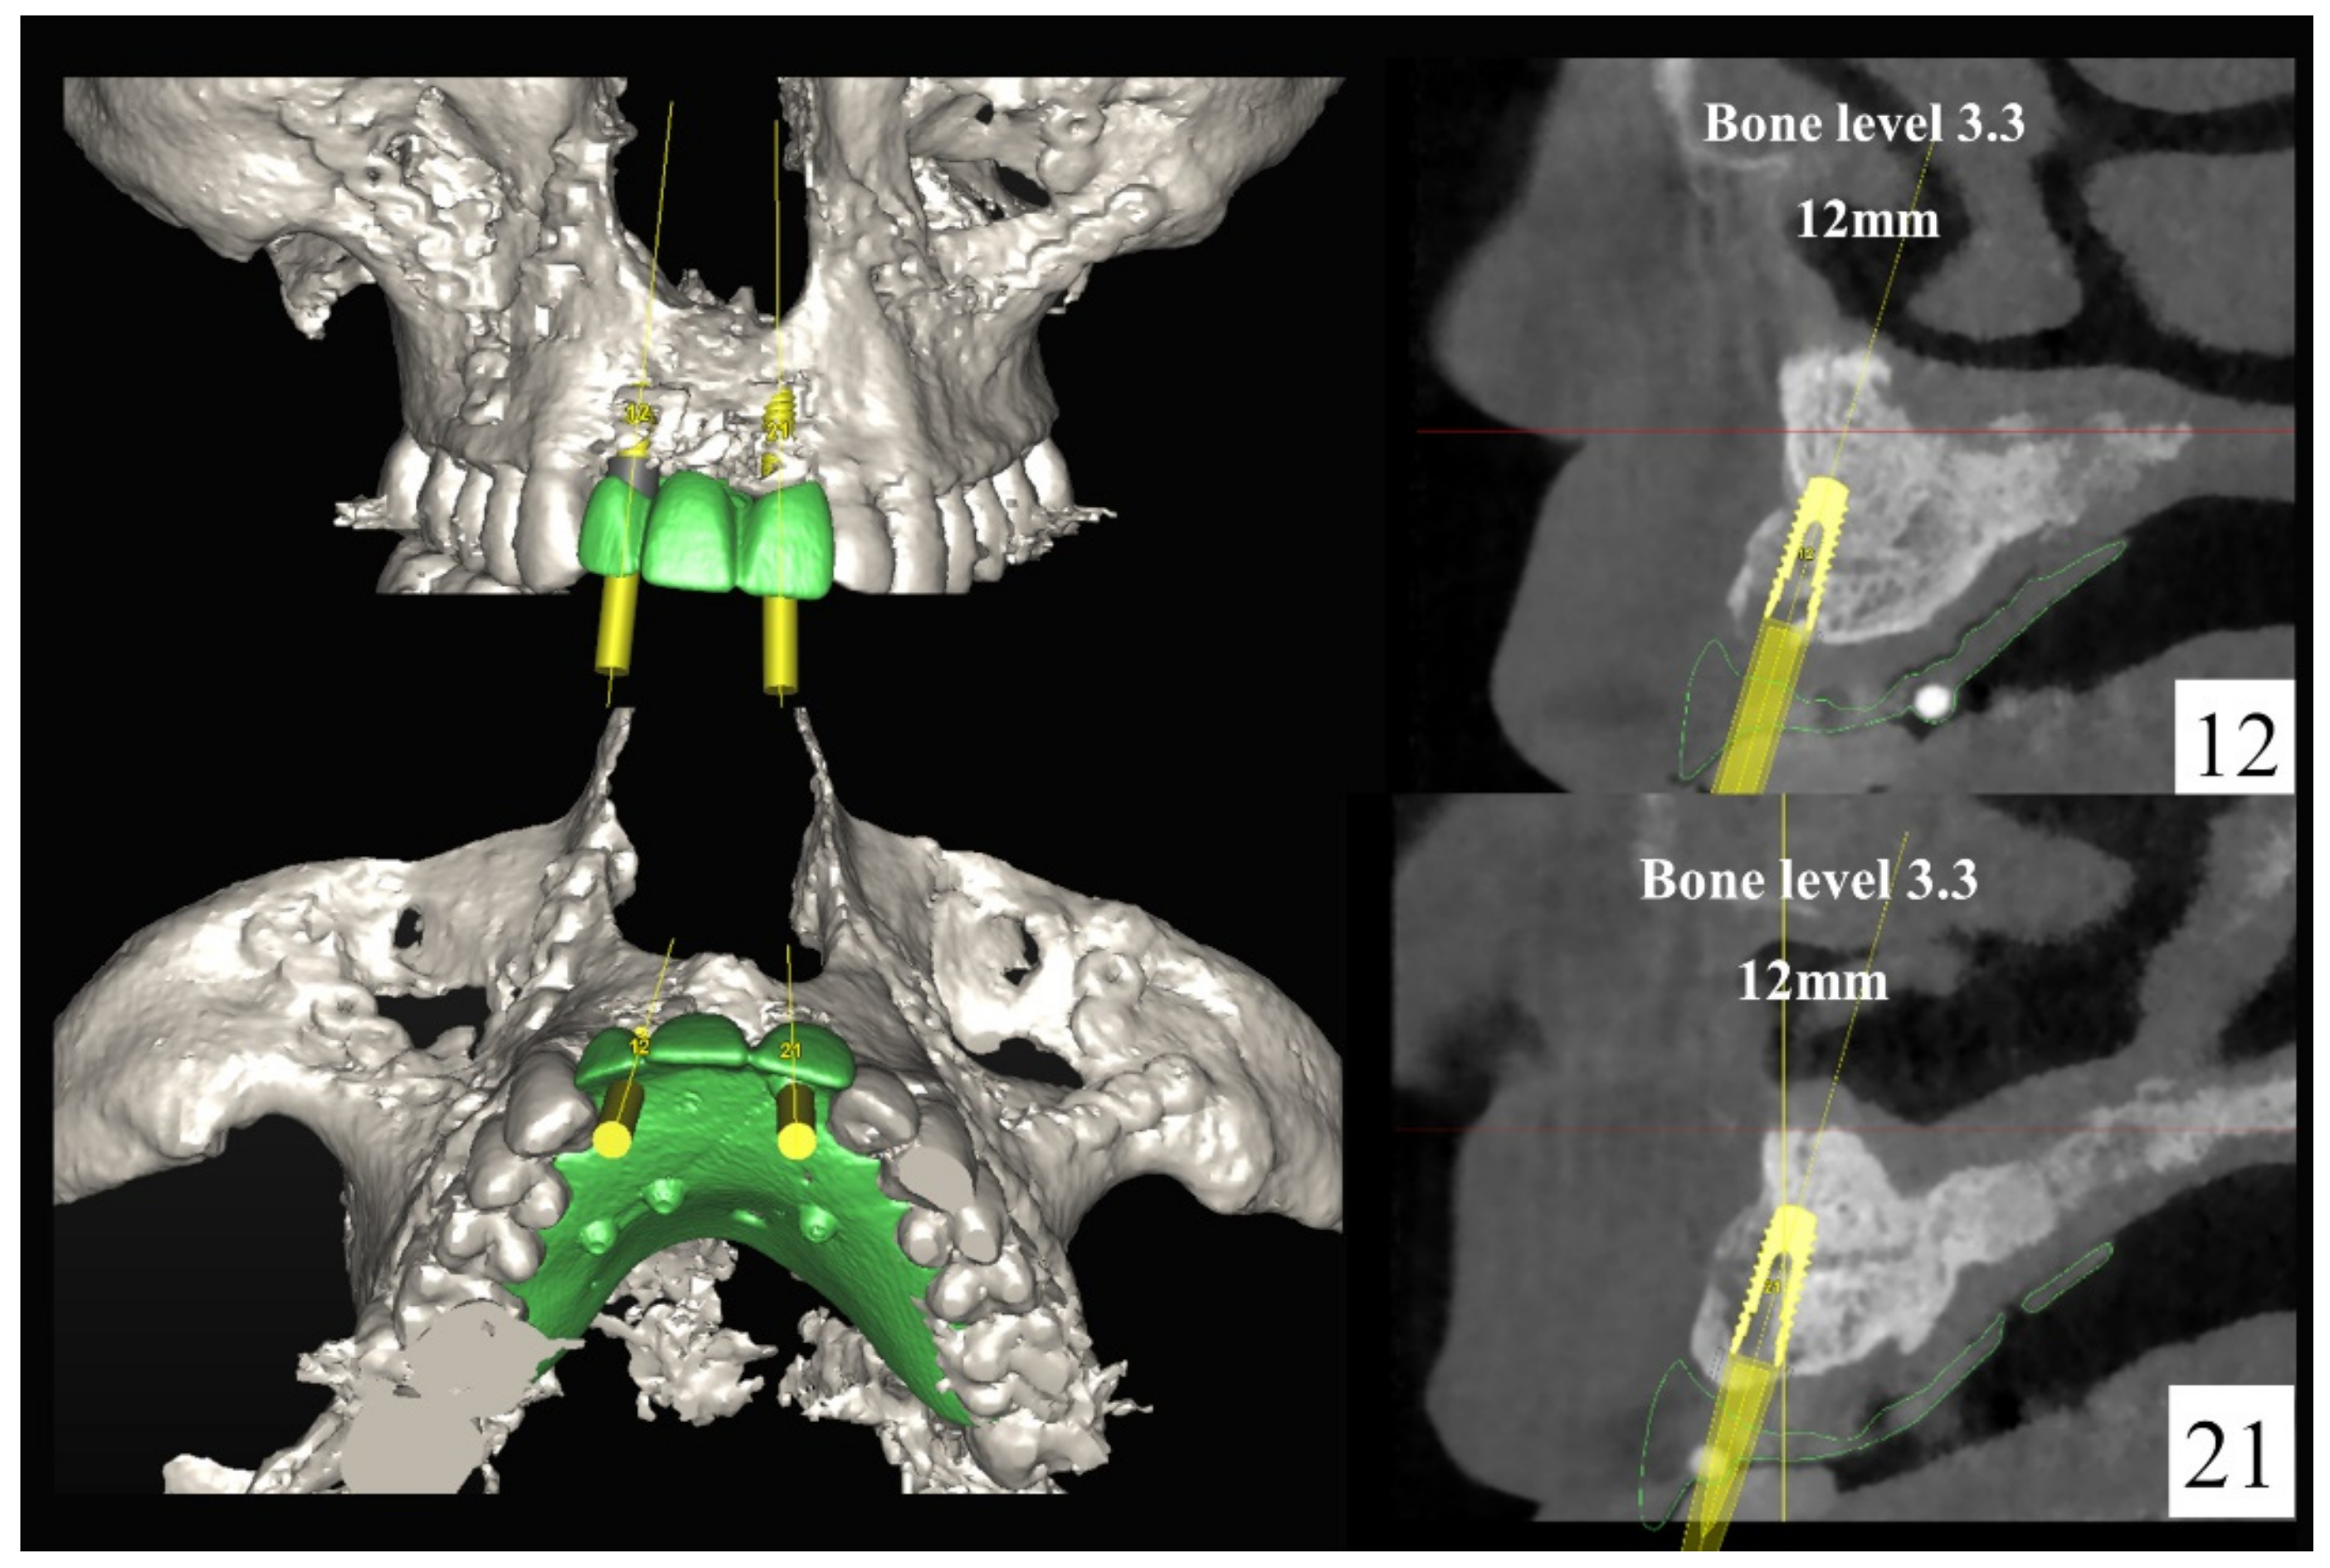

Figure 4.

Planning of the number, the diameter, and the axis of the implant with respect to the design of the final prosthesis.

In November 2017, two guided dental implants were placed at sites # 12 and # 21 (Figure 7, Figure 8, Figure 9, Figure 10 and Figure 11).